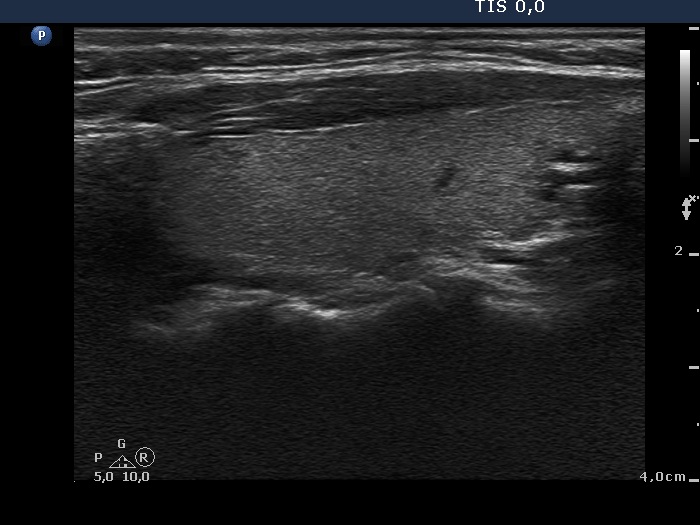

Second examination 9 months later (2nd row of images)

Clinical data: The patient had no complaints except for a 6 kg weight in gain.

Palpation: unchanged.

Results of blood tests: euthyroidism on daily 10 mg methimazole (TSH 3.58 mIU/L, FT4 12.7 pM/L).

Ultrasonography: Compared with the first examination, the thyroid has decreased in size and the echo structure became less hypoechogenic. The vascularization remained unchanged.

Suggestion: daily 5 mg methimazole.